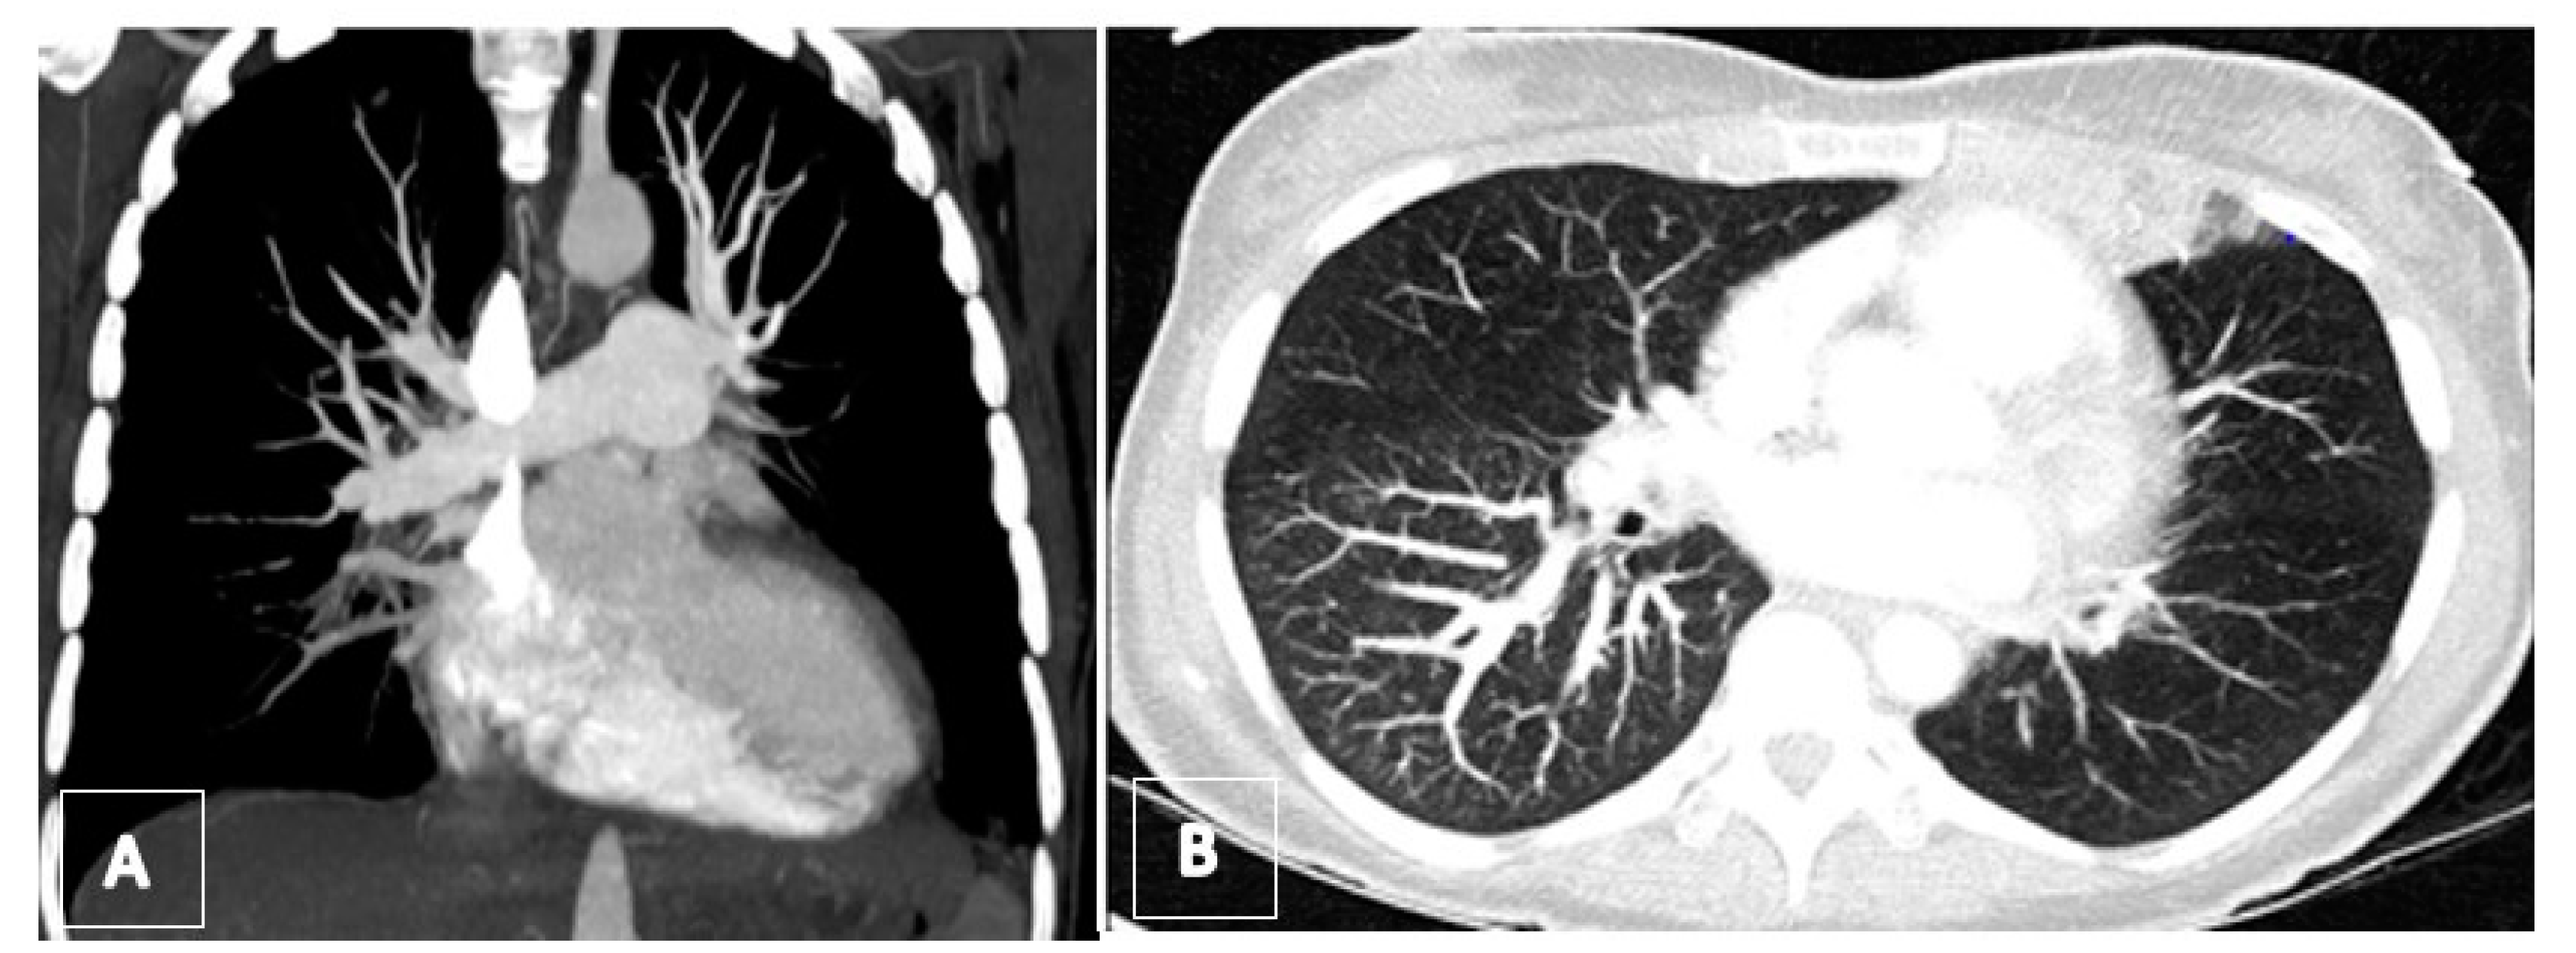

3.4. Computed Tomography Pulmonary Angiography (CTPA)

3.5. Transthoracic Echocardiography